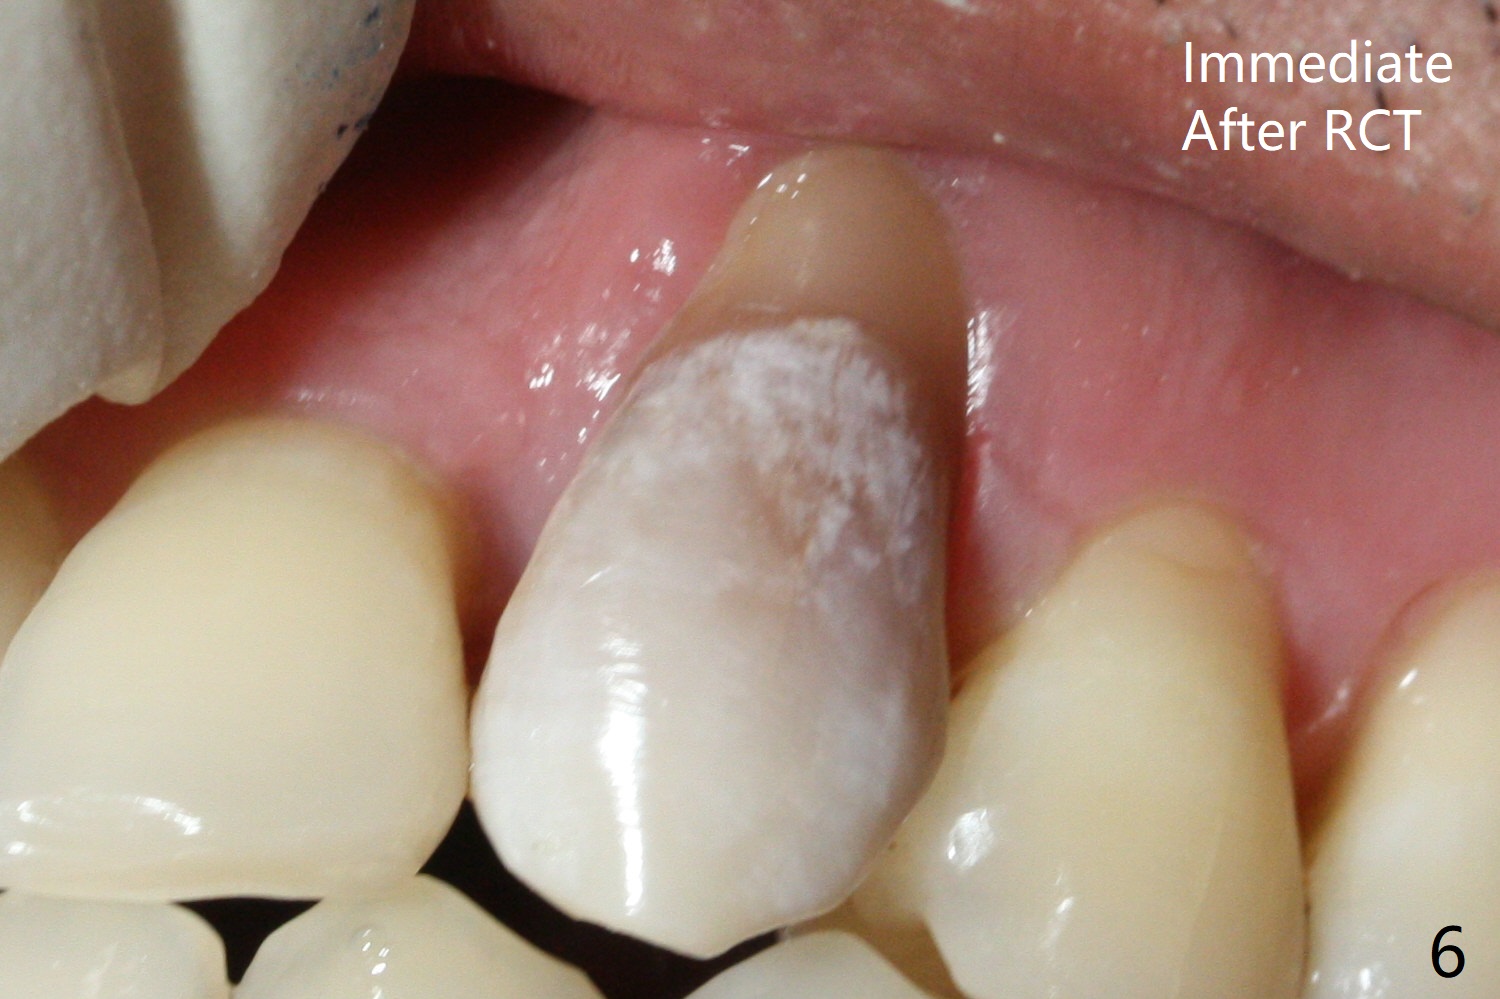

A 45-year-old man had severe malocclusion and chose non-extraction orthodontic treatment (Fig.1 (2012)). Five years later, the tooth #11 discolors (Fig.3, as compared to #6 in Fig.2). Immediately after RCT (Fig.4,5), the affected tooth has sudden change in shade (Fig.6). Two weeks later there is rebound in shade (Fig.7). The latter improves after two rounds of chair-side internal bleaching with 35% Hydrogen Peroxide for 20 minutes and build-up with the lightest shade composite (Fig.8). For optimum, place the bleach gel in the pulpal chamber and close the access with Cavit for a few days. In fact the latter is unnecessary. The treated tooth looks as normal as the tooth on the other side 1 year 10 months post whitening (Fig.9). PARL reduces 3 years post RCT (Fig.10 <, as compared to Fig.5).